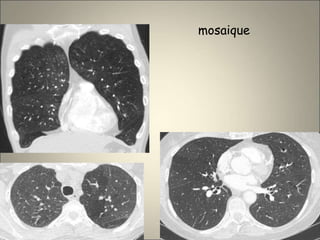

Atteinte des petites voies aériennes

• Poumon en mosaïque sans destruction de

l’architecture pulmonaire (obstruction

bronchiolaire inhomogène )

mosaique